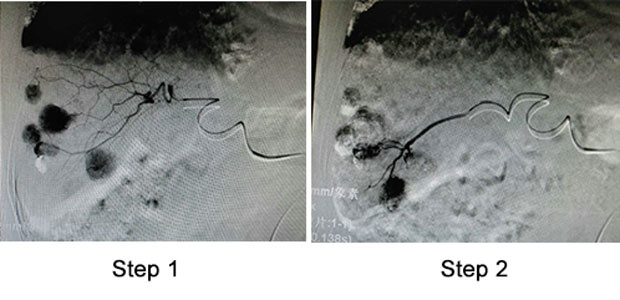

During the operation, the doctor firstly conducted femoral artery puncture with local anaesthesia to patient., channeling the front end of catheter into celiac artery, proper hepatic artery and arteries on both left and right liver to detect the tumor lesion.

Secondly, the doctor identified each supplying artery by catheter and performed drug injection and embolism.

Thirdly, performed radiotherapy a second time, in which indicating that the lipiodol was well deposited and the tumor stain disappeared, tumor lesions were perfectly covered by drugs.